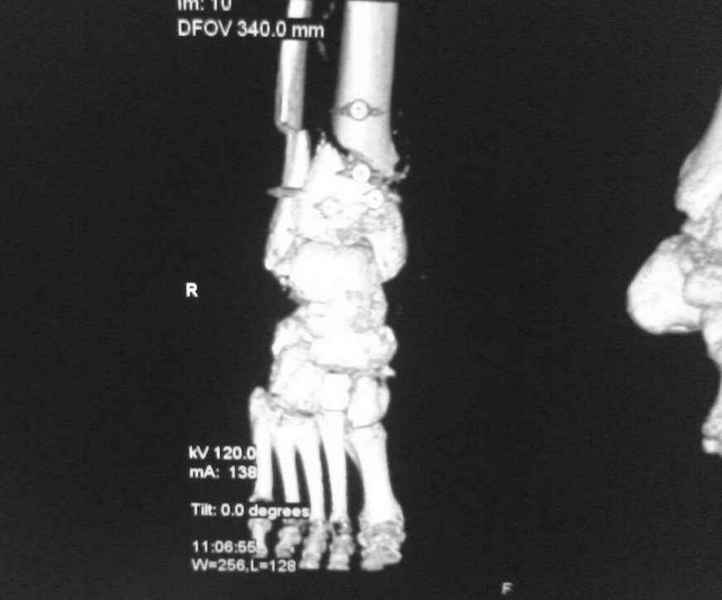

[Ortho] [1/2] Метатарзал краш синдром в порочном сращении (эквинусная стопа), несращение сегментарного перелома костей голени после БИОС , ПТФБ, ХВН СЕАР С-6.

Больной 39 лет. Травма получена в ДТП 21.09.09г. был госпитализирован в обл. больницу

соседней области с диагнозом сочетанная травма зчмт сотрясение головного мозга

сегментарный перелом костей правой голени с\3-н\3, суральный флеботромбоз циркулярные

некрозы н\3 правой голени правого голеностопного сустава лечение скелетным вытяжением за

пяточную кость. переведён в наше отделение 6.10.09г. возобновлено скелетное вытяжение,

перевязки, иссечение некрозов, антикоагулянты. На уздг диагноз флеботромбоза

подтвержден. 28.10.09 операция БИОС правой б\берцовой кости штифтом PTNL остеомед .

остеосинтез м\берцовой кости не выполняли из-за наличия гранулирующих ран и некрозов в

месте операционного доступа. Вторым этапом планировалось наложить аппарат Илизарова для

выведения стопы из эквинуса и динамизации штифта. Но из-за наличия гранулирующих ран и

некрозов в местах проведения спиц на стопе и голени 19.11.09 переведен в ожоговое отделение

для САДП гранулирующих ран после некрозов. 23.11.09 САДП. В послеоперационном периоде-

длительное заживление ран с лизисом кожных лоскутов, манифестное развитие ХВН с

формированием трофических язв и лимфэдемы. Больной явился на госпитализацию 13.01.10г.

локальный статус и свежие снимки прилагаю. Данные уздг выложу позже. Что в этой ситуации

делать я не знаю. Признаков сращения на Rg-нет плюс метафизарный фрагмент кивнул на вальгус.